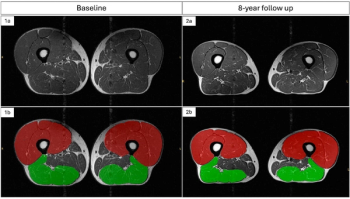

For overweight and obese patients at risk for knee osteoarthritis (OA), eight-year follow-up MRI data revealed a 12.8 percent loss of thigh muscle sub-volume for people who had extensive weight loss in comparison to 5.1 percent for those who retained a stable weight.